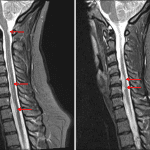

- Multiple T2/STIR hyperintense, short segment lesions in the cervical spinal cord including a midline dorsal lesion at the level of C1, a left lateral lesion at the level of C2-C3, a left dorsal lesion at the level of C3, a right lateral lesion at the level of C5-C6, a left lateral lesion at the level of C6, and a right ventrolateral lesion at the level of C7-T1

- Associated focal intramedullary enhancement on the left at C2-C3 and on the right at C6

- Normal cord contour and volume

- Multiple sclerosis

Multiple T2/STIR hyperintense, short segment lesions in the cervical spinal cord including a midline dorsal lesion at the level of C1, a left lateral lesion at the level of C2-C3, a left dorsal lesion at the level of C3, a right lateral lesion at the level of C5-C6, a left lateral lesion at the level of C6, and a right ventrolateral lesion at the level of C7-T1. This appearance is most consistent with a demyelinating process, particularly multiple sclerosis. Enhancement associated with lesions on the left at C2-C3 and on the right at C6 suggests active demyelination. Recommend brain MRI with and without contrast to assess for intracranial disease.